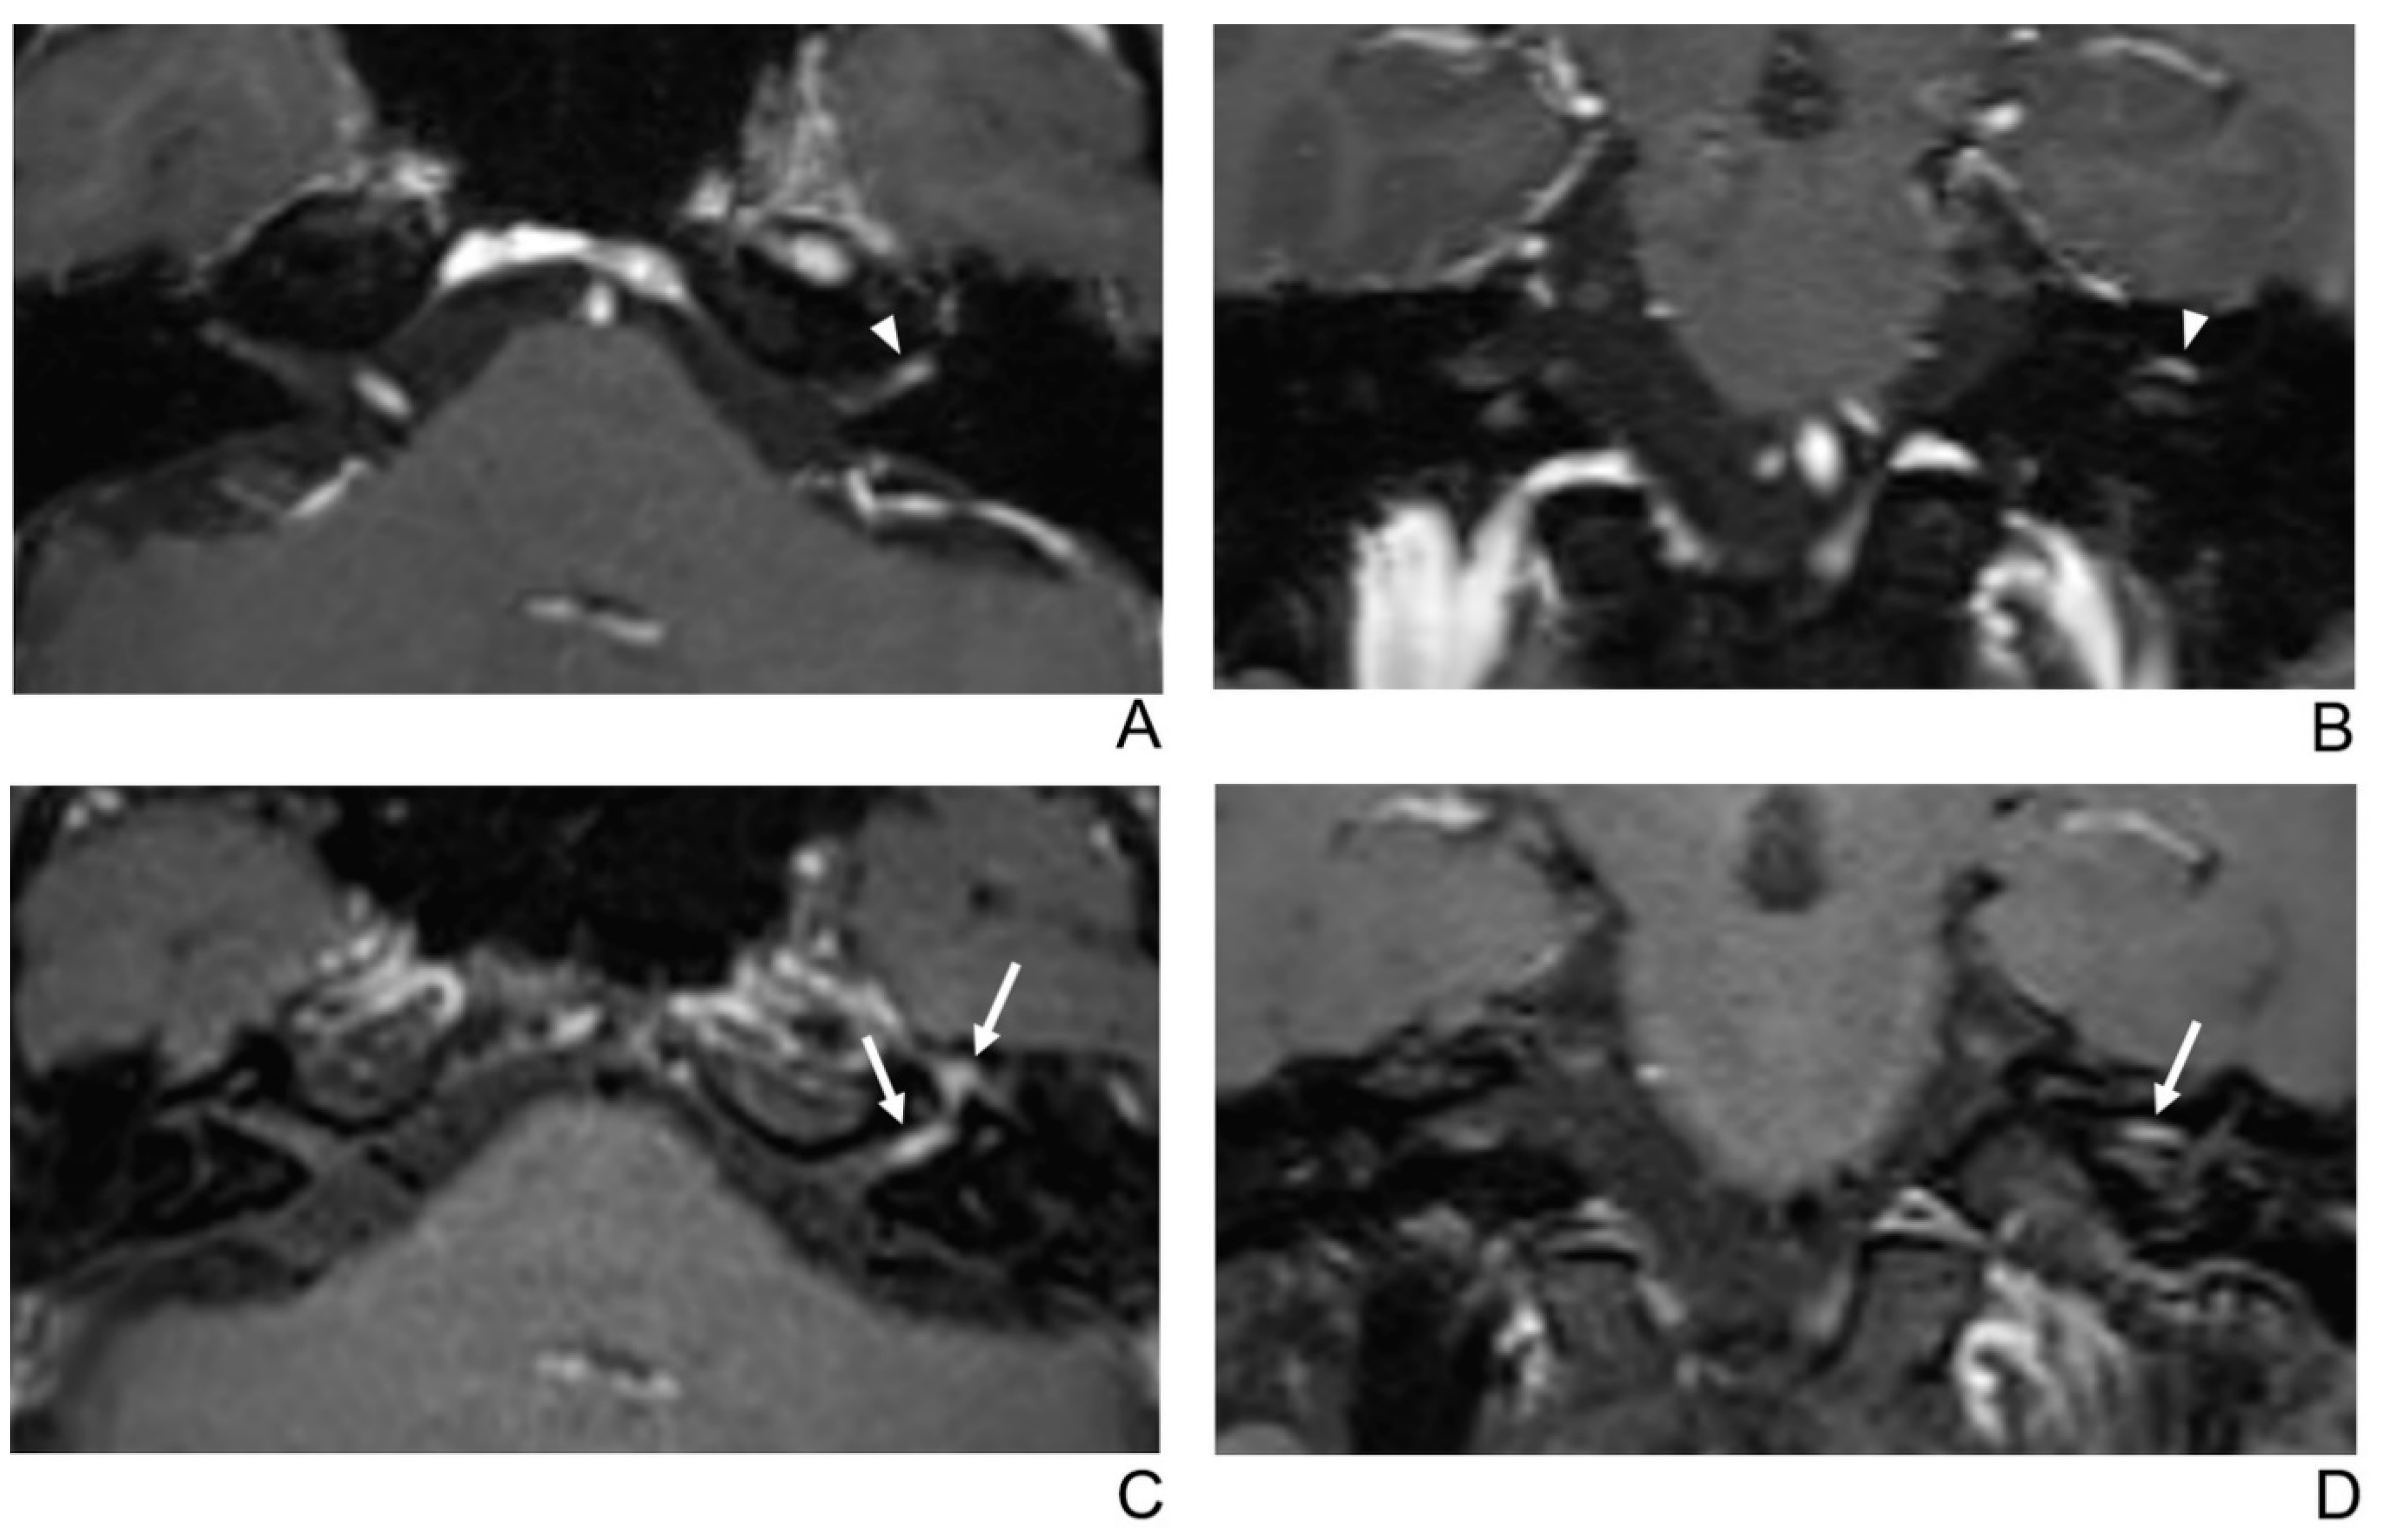

Figure 3.

A 29-year-old male patient with left facial neuritis. (A–D) Paired axial and coronal CE-GRE (A,B) and T1 BB-FSE (C,D) images of the same patient. The left distal canalicular segment of the facial nerve showed faint enhancement in the axial (A) and coronal (B) CE-GRE images (arrowheads). Those images were interpreted by reviewers 1 and 2 as suspicious left facial neuritis (1, diagnostic confidence; 1, 0, and 1, visual grades for contrast enhancement (CE) in the canalicular, labyrinthine, and anterior genu segments, respectively). In contrast, the left facial nerve shows asymmetric, intense enhancement in the canalicular, labyrinthine, and anterior genu segments in the axial (C) and coronal (D) T1 BB-FSE images (arrows); it was evaluated by reviewers 1 and 2 as left facial neuritis (2, diagnostic confidence; 3, visual grade for CE in all three segments).